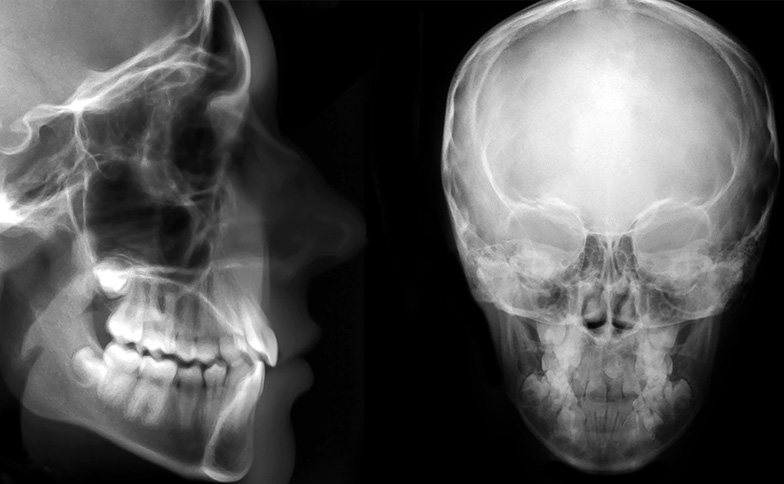

歯を抜かずにスペースを作る手法の一つに、奥歯(大臼歯)を後方へ移動させる「遠心移動」があります。これが可能かどうかは、精密なセファロ分析(顔面のレントゲン分析)による数値的な根拠に基づいて判断します。

PTV(翼突上顎垂直面)からの距離

上顎の奥に、歯が移動できるだけの「堤防(骨の奥行き)」がどれくらいあるかを測定します。

数値が大きい場合

奥歯を後ろへ動かせる可能性が高く、非抜歯矯正の適応となる期待が持てます。

数値が小さい場合

スペースが不足しており、無理に動かすと一番奥の歯(第二大臼歯)が埋まったままになったり、正しく生えてこなかったりするリスクがあります。

PM line(翼突下顎線)と歯の位置

将来的に歯が並ぶスペースは、成長とともに変化します。検査時、奥歯の芽(歯胚)がこのラインより前方にあれば、非抜歯で治療できる可能性が高いと判断されます。